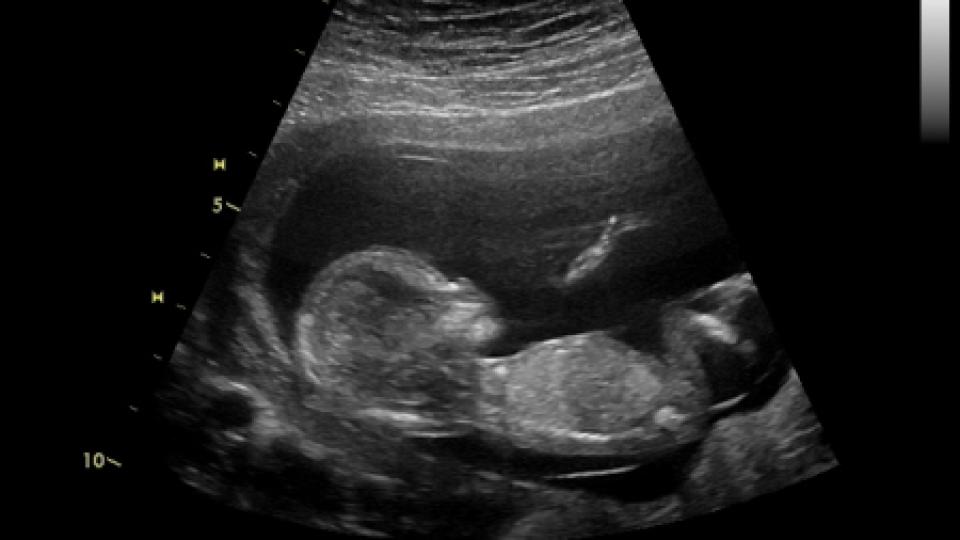

Неродено дете спаси живота на собствената си майка. 29-годишната Ясмин Рандал от английския град Саутхамптън не подозирала, че страда от смъртоносно заболяване, докато в осмата седмица от бременността не се подложила на видеозон, на който лъснала страшната истина - че има злокачествен тумор.

По време на прегледа лекарката потвърдила, че плодът в утробата на Ясмин се развива нормално, но попаднала на нещо много притеснително в пикочния й мехур. "Сонографът показа, че бебето ни е напълно добре. И двамата със съпруга ми бяхме толкова развълнувани да видим как сърцето й бие, че не забелязахме, че лекарката се забави при сканирането. Когато по-късно ми каза, че е видяла някакво образувание в пикочния ми мехур, и двамата изпаднахме в шок", спомня си госпожа Рандал.

"Бяхме много щастливи, когато една седмица по-късно на видеозона видяхме, че Лоти размахва малките си ръчички и краченца", добавя с умиление Рандал.